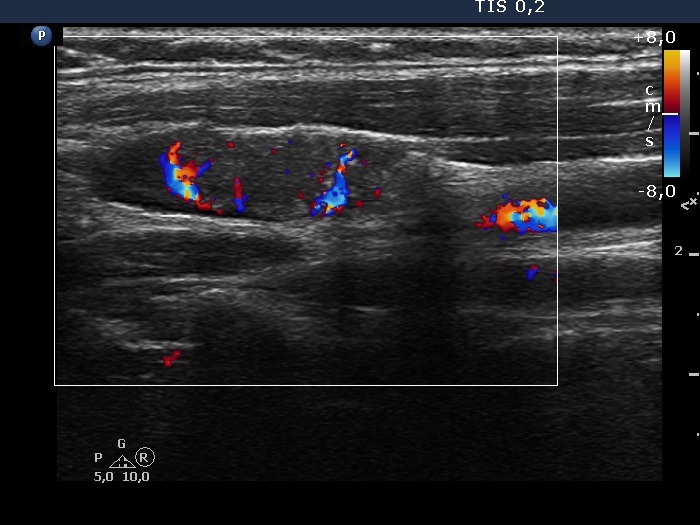

Right lobe, longitudinal scan

Above the right lobe, longitudinal scan, color Doppler mode. The vascularization of the nodule is irregular.